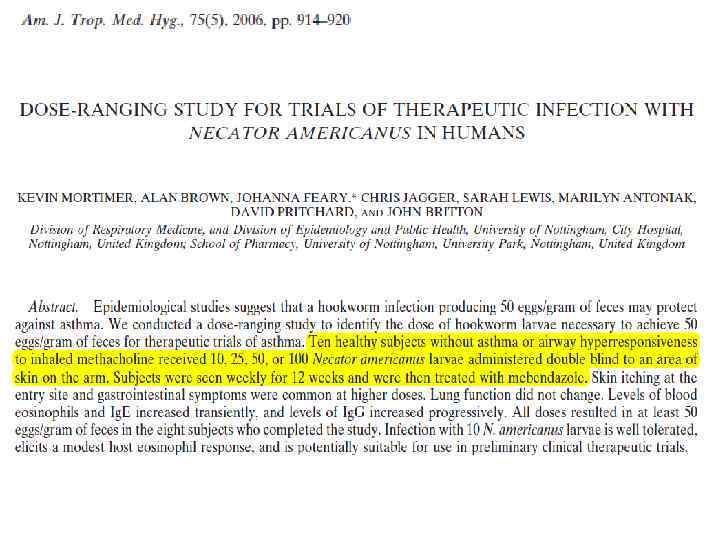

Терапия гельминтами – разновидность иммунотерапии – лечение аутоиммунных заболеваний и некоторых других иммунопатологических процессов с использованием определённых гельминтов или их яиц. Применяются три варианта терапии: с помощью личинок некатора, яиц Trichuris suis или яиц Trichuris trichiura. Режимы такого лечения разработаны для болезни Крона, неспецифического язвенного колита, рассеянного склероза, бронхиальной астмы, экземы, дерматитов, поллиноза и пищевых аллергий.

Scientists have been trying to figure out why diseases that affect the immune system have increased dramatically over the past several decades in much of the developed world. For example, the incidence of asthma in U. S. children under 17 was up 28% in 2009 from 1999, according to government data. The whipworm treatment was born from a theory known as the hygiene hypothesis, which essentially says our environment has become too clean. Humans aren't exposed to microorganisms in the environment as much as they used to be, when more people farmed or lived closely with animals. While many diseases have diminished thanks to improved hygiene and medicine, people aren't exposed to bacteria that helped regulate the immune system, theory goes. This lack of exposure may, in part, be responsible for the increase in diseases in which the body's immune system goes awry.

The so-called ‘‘hygiene hypothesis’’ states that since gastrointestinal helminths are among those pathogens likely to have coevolved over the longest period of time with their hosts, lack of exposure to these organisms early in life in developed societies may predispose certain individuals to immunopathological conditions such as those listed. There are strong epidemiological correlates between low exposure to helminths and high levels of allergic/immunopathological conditions within individual societies (G. Mulcahy, S. O’Neill, S. Donnelly, J. P. Dalton. Adv Drug Delivery Rev 56 (2004) 853– 868)